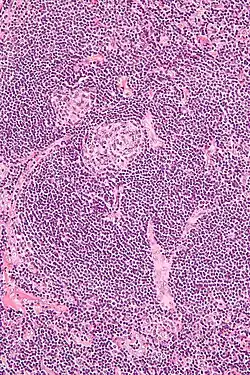

Histologie

Histologisch besteht der vergrößerte Lymphknoten aus einer deutlich vermehrten Anzahl von Lymphfollikeln, die Sinus sind durch die Expansion der Follikel vermindert oder nicht mehr erkennbar, und die Kapsel ist verdickt. In den Follikeln sind die Keimzentren atroph oder regressiv verändert. Es finden sich aber oft mehrere Keimzentren in einer Follikel-Mantelzone, sog. twinning. Gelegentlich kann man senkrecht in den Follikel eintretende hyalinisierte Gefäße erkennen, sog. Lollipop-Phänomen. Die Mantelzone ist verdickt und hat ein zwiebelschalenartiges Aussehen (onion-skinning). Dies entsteht durch eine Ansammlung von Mantelzonen-Lymphozyten entlang der follikulären dendritischen Zellen rund um die atrophen Keimzentren. In der interfollikulären Zone finden sich vermehrt endotheliale Venolen sowie kleine Lymphozyten und gelegentlich Plasmazellen.

Während alle beschriebenen histologischen Veränderungen einzeln auch bei anderen reaktiven und neoplastischen Lymphknotenveränderungen (wie Lymphomen) vorkommen können, ist ihr Zusammentreffen typisch und diagnostisch für den Morbus Castleman (ICD-10: D36.0)